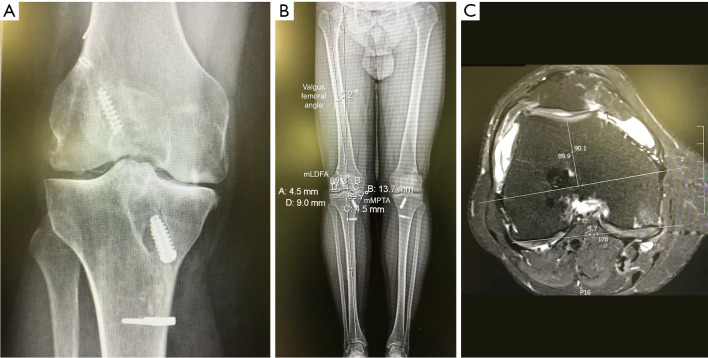

Abstract Image